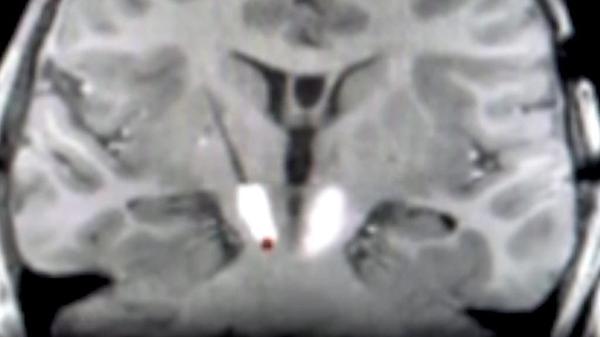

Advances in gene therapy research offer new insights into brain tumors and disorders

For patients with rare and devastating neurological disorders, treatment options can seem few and far between. However, gene therapy research, led by Dr. Russell Lonser and Dr. Brad Elder, is hoping to offer better care.

Lonser is the director of the Gene Therapy Institute at Ohio State, and Elder is the director of Neurosurgical Oncology. Their work focuses on treating disorders like Alzheimer’s and Parkinson’s Disease, both of which affect over 8 million Americans combined, by injecting healt...